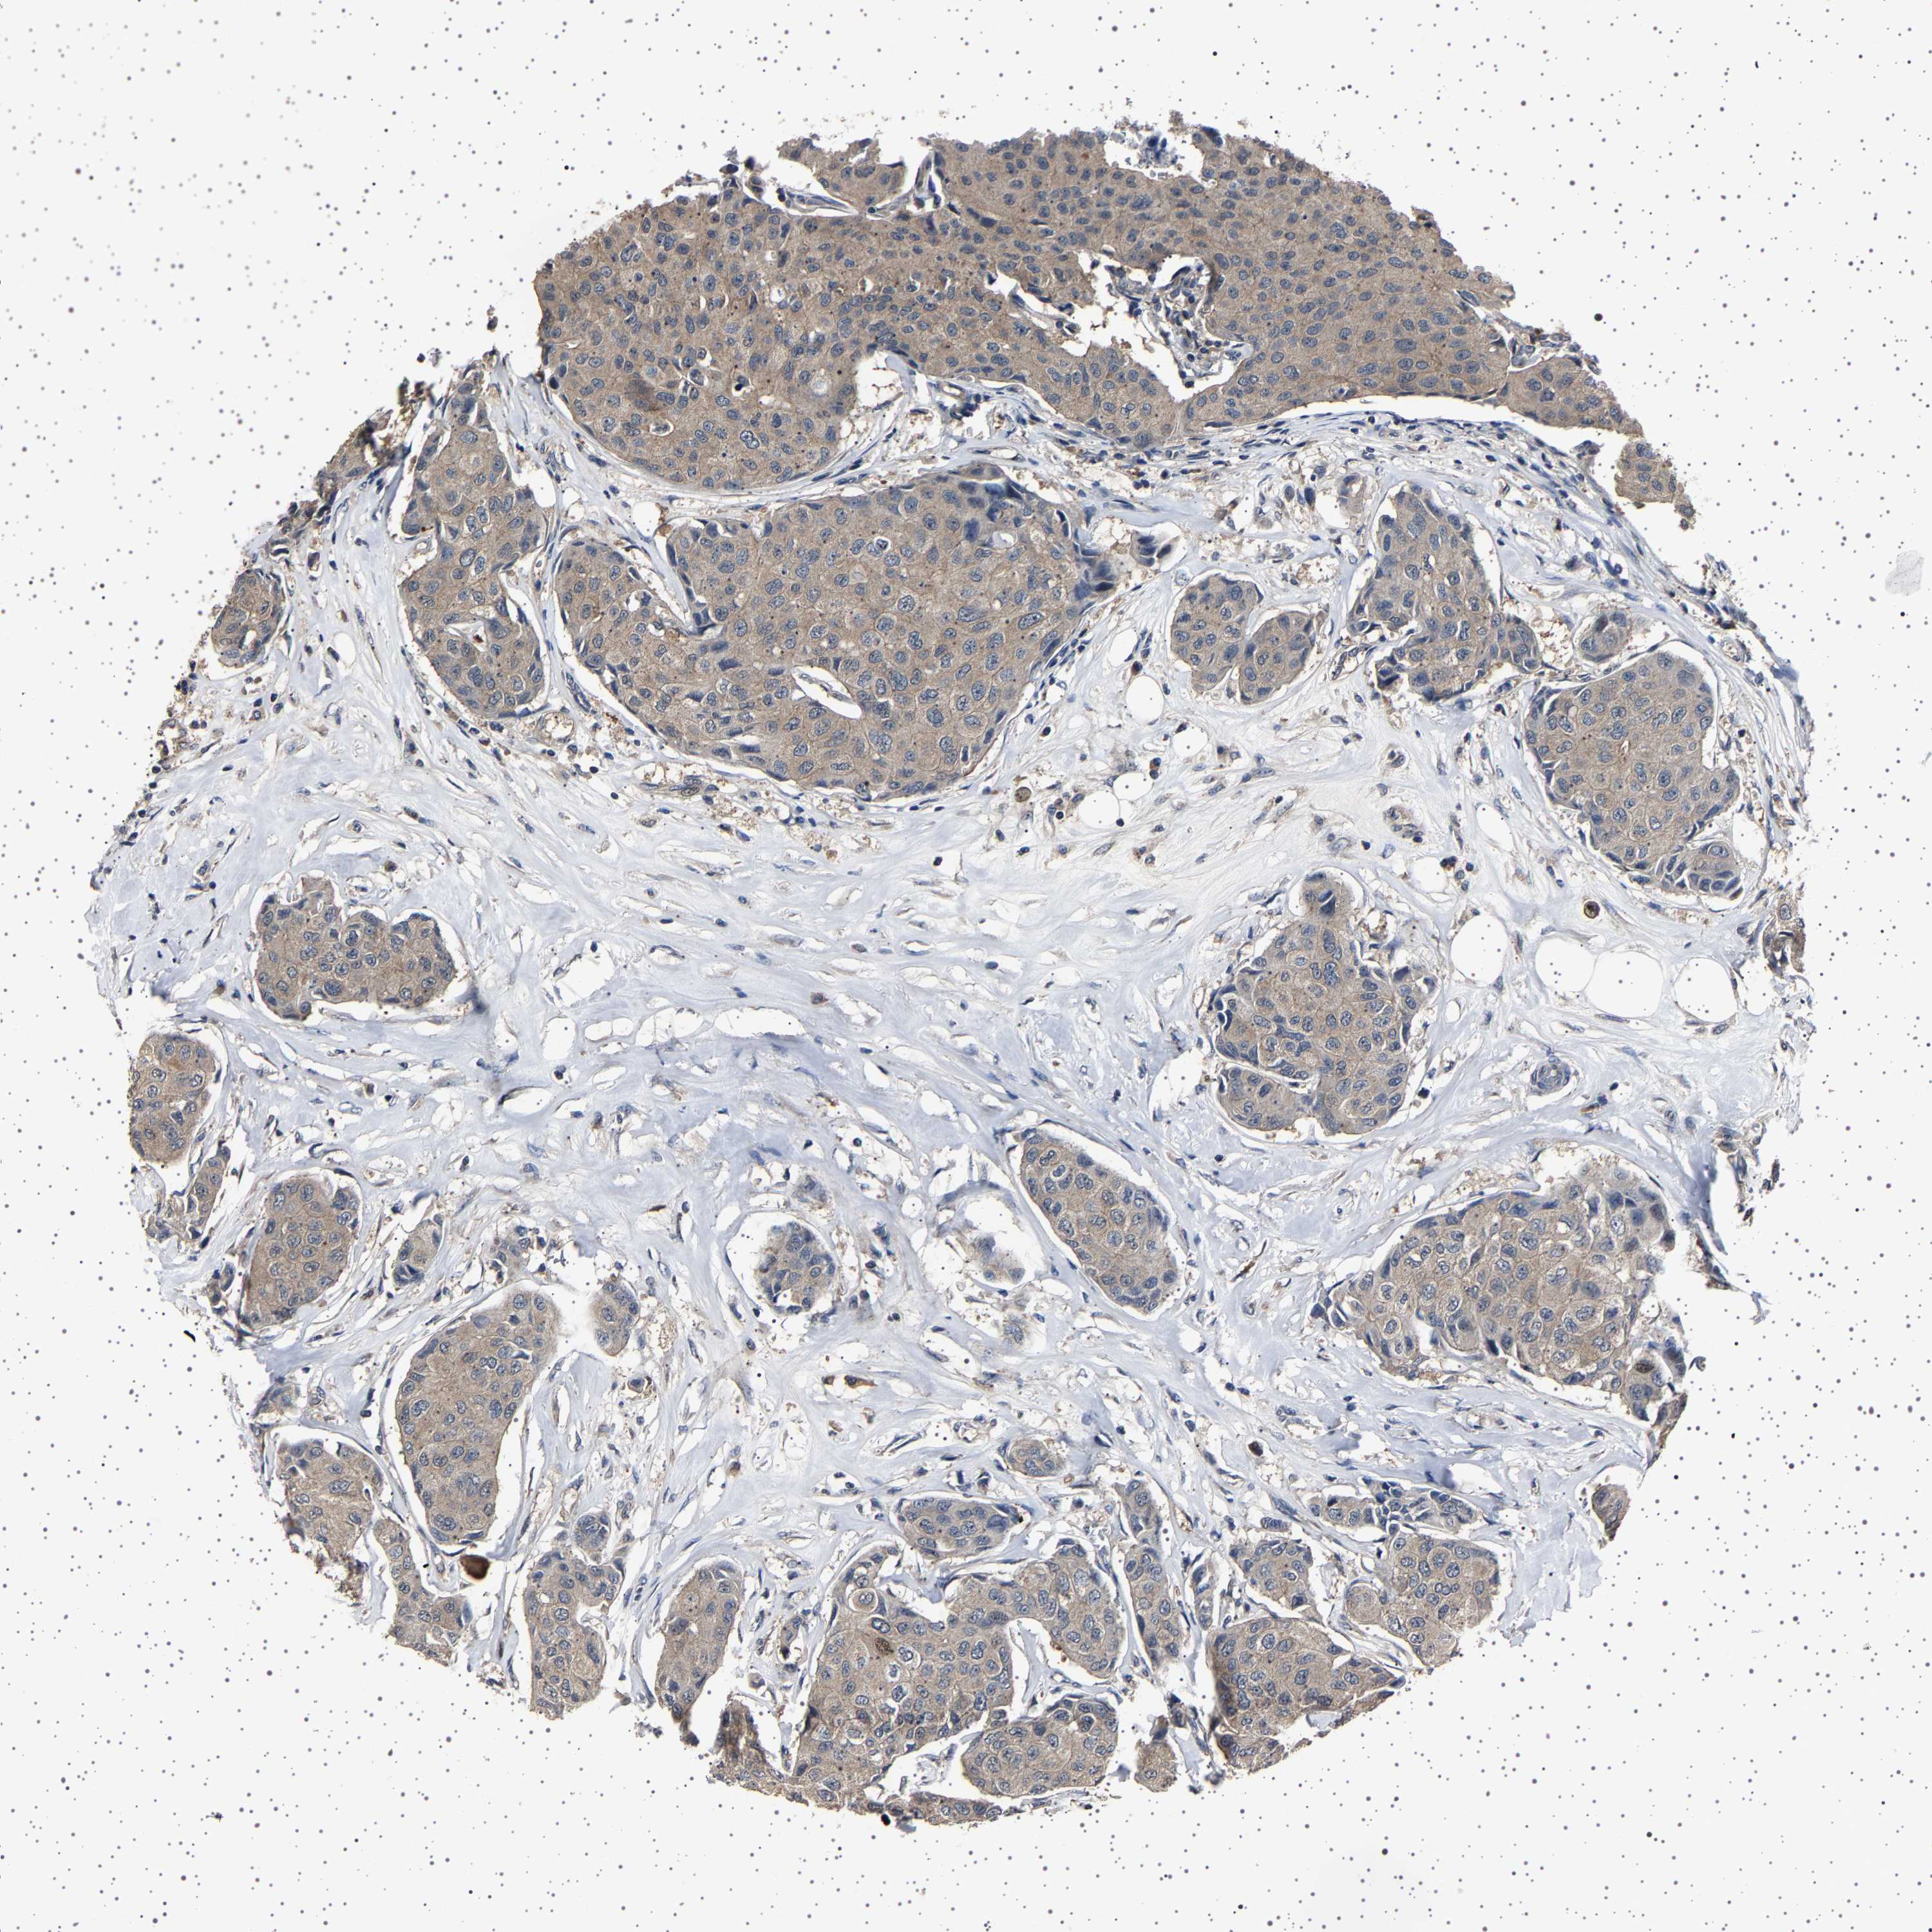

CANCER BREAST CANCER Show tissue menu

BRCA TCGA BRCA VALIDATION PROTEIN EXPRESSION